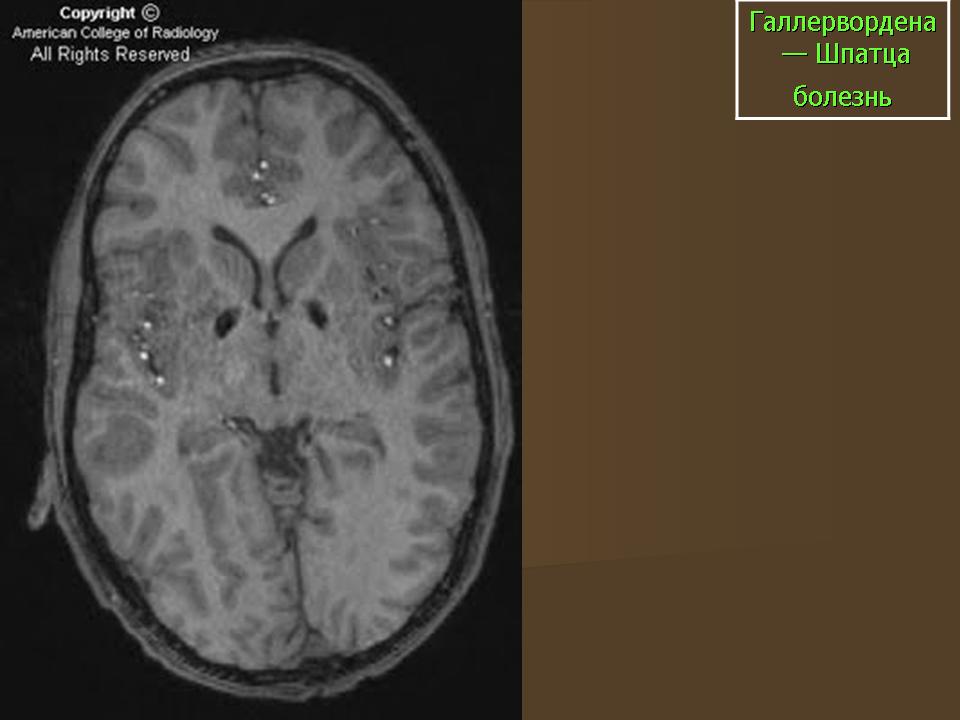

ГМ. Галлервордена - Шпатца болезнь. +

Галлервордена - Шпатца болезнь

Болезнь Галлервордена - Шпатца - наследственное заболевание экстрапирамидной системы, связанная с нарушением обмена железа и липидов и повреждением бледного шара и черной субстанции. Тип наследования аутосомно-рецессивный. При патоморфологическом исследовании характерным признаком является гиперпигментация бледного шара и черной субстанции. Обнаруживается пигментация коры полушарий большого мозга и таламуса. Пигмент находится внутри невронов и глиальных клеток, расположенных около сосудов; содержит железо (вместе с тем каких-либо нарушений обмена железа в организме не обнаружено). Наблюдаются утолщение и фрагментация аксонцилиндров в пораженных областях. Постепенно наступает дегенерация невронов коры полушарий большого мозга и мозжечка. Характеризуются нарастающей экстрапирамидной ригидностью, гиперкинезами (атетоз, торсионная дистония), затем развивается акинетико-ригидный синдром, пирамидная микросимптоматика, снижение интеллекта. Течение медленно прогрессирующее на протяжении 10 - 20 лет.

"Глаз тигра"-наглядно и красиво.